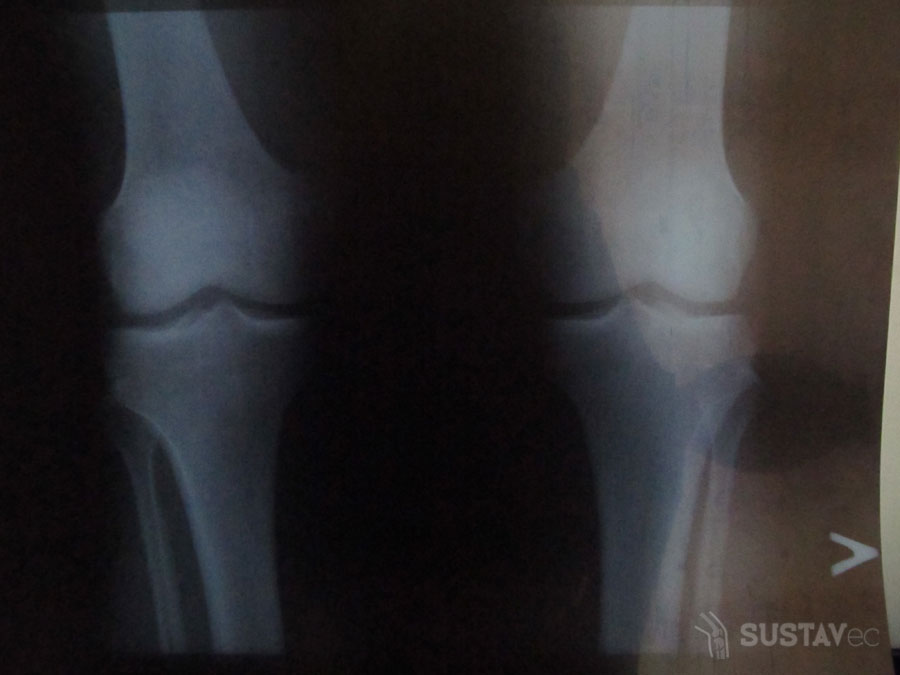

Иногда после рентгеновского снимка коленных суставов в заключении можно прочитать, что выставлен диагноз «лигаментоз». Какая разница между лигаментозом и лигаментитом? При лигаментозе имеет место уплотнение связочной ткани, повышение ее хрупкости вследствие избыточной минерализации или отложения солей. Этот процесс обызвествления связок наиболее часто протекает при нарушении обмена кальция в организме, например, при патологии паращитовидных желез. Лигаментит колена при рентгеновском исследовании будет «прозрачной» патологией, а при лигаментозе возникнут рентгеноконтрастные тени связок. Какими способами еще можно поставить диагноз?

В настоящее время основой диагностики являются визуализирующие исследования, такие как УЗИ сустава и МРТ. В том случае, если подозревается наличие конкрементов и обызвествления, это будет хорошо заметно при проведении обычной рентгенографии в двух проекциях.